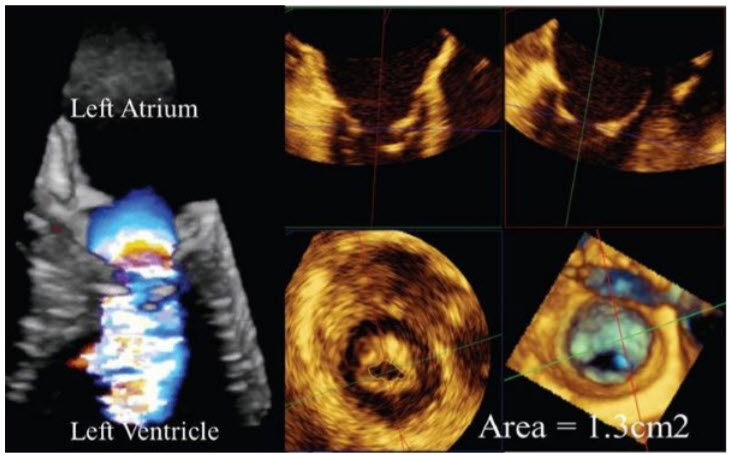

An echocardiogram is performed (Fig. below);

Proximal flow convergence radius (PFCR) using color 3D across the mitral valve indicates an orifice area of 1.2 cm2 . Resting PA pressures are 35 mmHg. Splittability score is 5. LV size and function are normal.